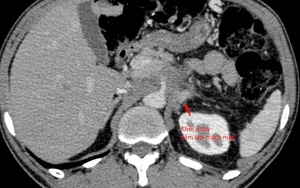

Sống khỏe 2025-12-24T16:32:00Một bệnh nhân nam đã tuyệt thực suốt 3 tuần với hy vọng “bỏ đói” khối u ung thư tụy. Tuy nhiên, kết quả không được như mong đợi.